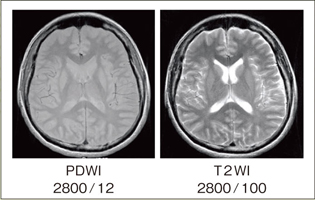

一般的に,Radial ScanによるFSE法では,T1強調画像,PD強調画像,STIRにおけるコントラスト低下の問題が指摘されています。これは,通常のFSE法と比較して,ブレードタイプのRadial Scanでは実効TE以外のエコーがk空間中央部分に配置され,コントラストが劣化するためです。RADARではこの影響を低減するために,k空間中央部分に特殊なフィルタを適用しています。図7にDual Contrast RADAR-FSEの画像を示します。良好なコントラストのPD強調画像が得られています。